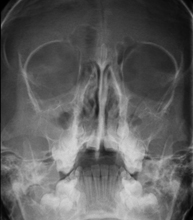

Tècnica que usa els raigs X a través de la qual s'obtenen imatges del crani per al seu estudi. Indicacions: traumatisme, tancament precoç de sutures cranials. - RX Sins Paranasals

Tècnica que usa els raigs X a través de la qual s'obtenen imatges dels sins paranasals per al seu estudi. Indicacions: dificultat respiratòria nasal, tos crònica, cefalea, mucositat - RX ATM (Articulació Temporo-Mandibular)